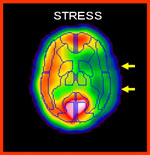

- 3.脳血流シンチ画像

(左:負荷時 右:安静時)